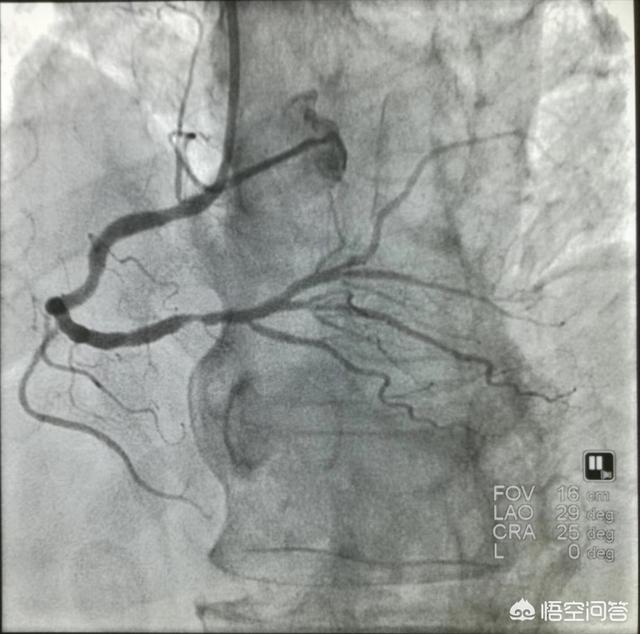

冠動脈造影検査が冠動脈疾患診断のゴールド・スタンダードであることは周知の事実であるが、結局のところ侵襲的な検査であるため、それをそのまま患者に適用することはできず、いつ、どのような病気であっても、複数の条件を統合して診断する必要がある。冠動脈疾患患者の最初の診断は症状であり、痛みの引き金となる要因の発現、時間、痛みの性質はすべて重要な意味を持ち、症状を分析することによって、基本的に患者の一部を除外することができる。そして、心電図、心臓色、CTなどの非侵襲的な検査を行います。すべての検査で冠動脈疾患が指摘された後、冠動脈造影検査を行って狭窄部位と程度を明らかにし、冠動脈疾患の診断を確定します。

冠動脈疾患の診断

もし急性心筋梗塞が起こったら、「時は命なり、時は心筋なり」を肝に銘じ、躊躇してはいけない、躊躇してはいけない、躊躇してはいけない、医師と協力し、できるだけ早く冠動脈造影、ステント留置(PCI)または血栓溶解療法で血管を開き、命を救う。